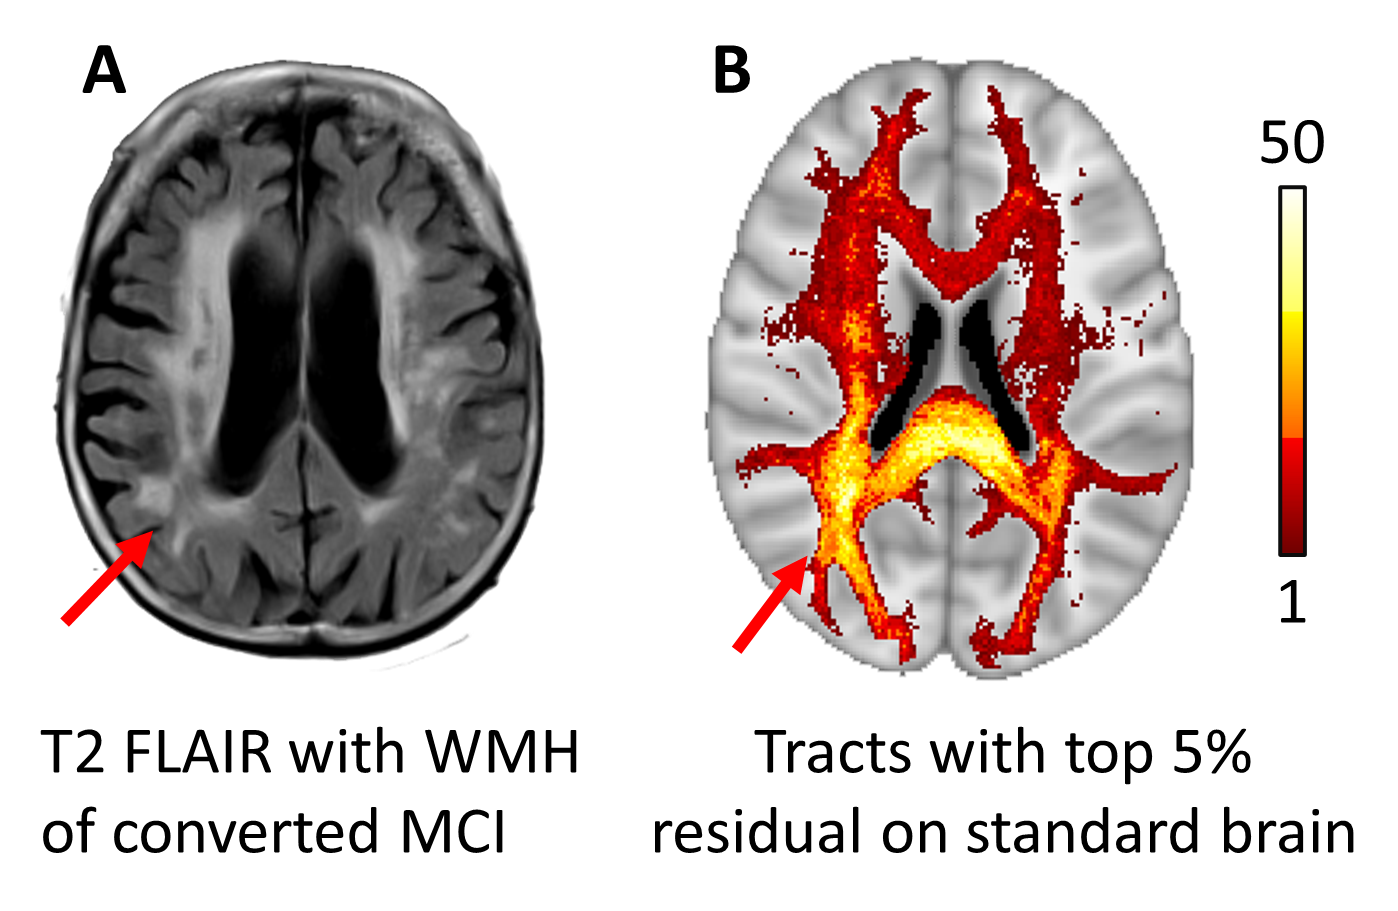

The interpretation approach produces a residual brain network with high dimensional features. For visualization purposes, we average the residuals of edge features, retain the edges with top 5%percent\% highest residuals, and present one case example in Fig 3. The interpretation results suggest that the proposed methodology is capable of capturing the abnormalities in brain networks from MCI-to-AD conversion, particularly the white matter hyperintensities related to cognitive decline.rticularly the white matter hyperintensities related with cognitive decline.

Refer to caption

Figure 3: Example of interpretation. A. A case example of a MCI patient who converted to AD. WMH(white matter hyper-intensity) is marked with red arrow. B. Distribution of tracts that are corresponding to the top 5%percent55\% residuals. Colorbar indicates number of edges crossing the voxel.